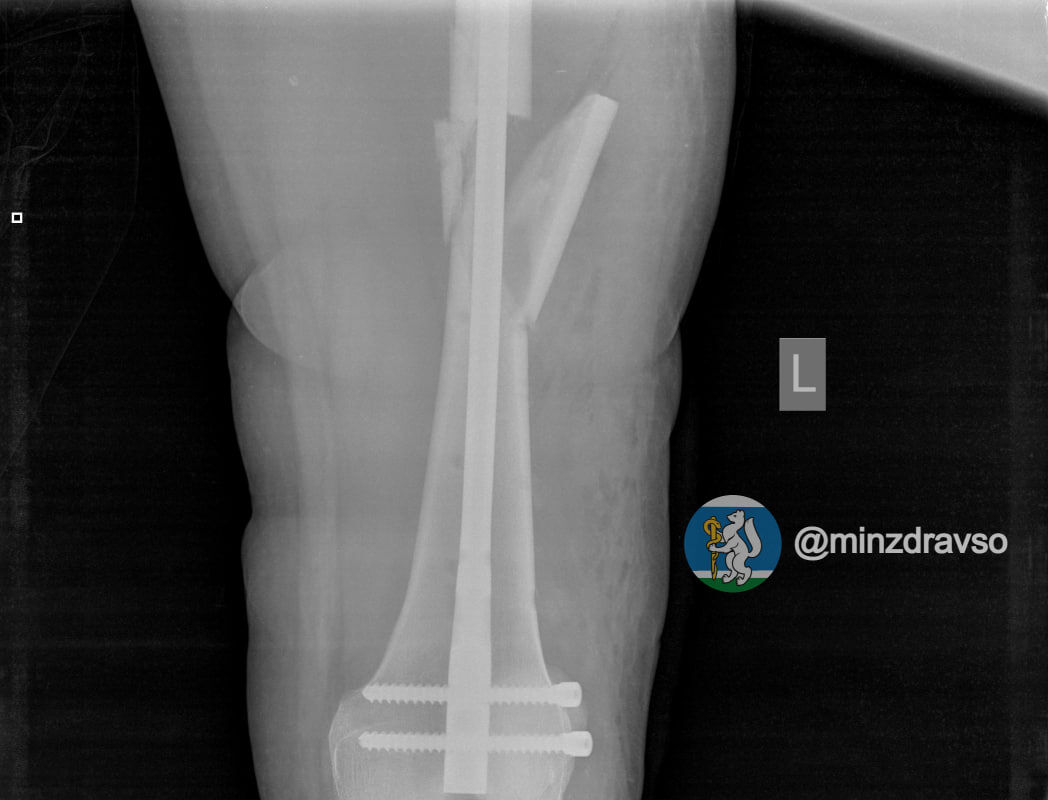

В Екатеринбурге 41-летняя беременная женщина упала с высоты десяти метров. В результате у нее диагностировали ушиб головы и сложный оскольчатый перелом левой бедренной кости, угрозы прерывания беременности медики не выявили.

Пациентке провели первую операцию в шоковой операционной приемного отделения. Через неделю, когда ее состояние стабилизировалось, женщине выполнили вторую операцию по замене аппаратов внешней фиксации на внутренний фиксатор. Для дальнейшего ведения беременности ее перевели в другую больницу.